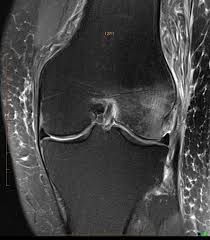

BML are typically not visible on X-rays. They are diagnosed using certain types of MRI, where they appear as a hazy white area against the background of darker bone. Pathologists have shown that these BML represent a healing response surrounding trauma, such as microtrabecular fractures of the subchondral bone.